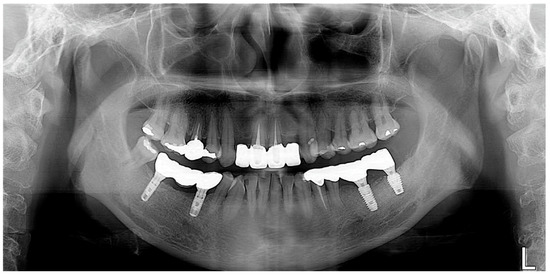

The final prosthesis was connected to the multi-abutment through the abutment screw in the oral cavity of the patient. After the intraoral adjustment, the prosthesis was connected to the implant through using an abutment screw with a torque of 25 N/cm2. The screw access hole was sealed using Teflon tape and composite resin (Gradia Direct A3, GC, Tokyo, Japan) to complete the procedure (Figure 6A), and the accuracy of the connection of the implant prosthesis was confirmed through a periapical radiograph (Figure 6B).

The final prosthesis was connected to the multi-abutments through the abutment screw in the oral cavity of the patient. After the intraoral adjustment, the prosthesis was connected to the implants through the abutment screw with a torque of 25 N/cm2. Teflon tape and composite resin were used to seal the screw access holes (Figure 11A) and the accurate connection of the implant prosthesis was evaluated through using a periapical radiograph (Figure 11B).

Figure 6. Final delivery of implant prosthesis. (A) Intraoral photograph, (B) Periapical radiograph.

Figure 11. Final delivery of implant prosthesis. (A) Intraoral photograph, (B) Periapical radiograph.